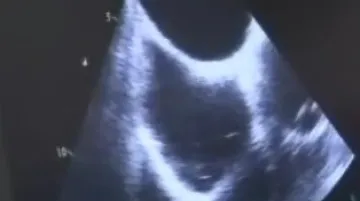

Podle Petra Kaly, vedoucího lékaře kardiologické kliniky, vyjde zákrok asi na 100 tisíc korun. Vhodný je pro pacienty, kteří mají chronickou fibrilaci síní. „To znamená, že srdíčko nepumpuje krev, jak má,“ popsal. V takzvaném oušku levé síně se méně vyměňuje krev a může tam vzniknout sraženina. Problém nastává, když se dostane do krevního oběhu.

Při operaci lékaři ouško uzavřou speciálním uzávěrem. Pacient je při operaci při vědomí, na sále stráví asi hodinu a půl, zákrok samotný trvá kolem 15 minut.